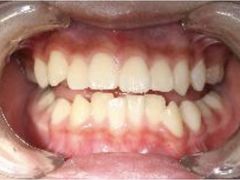

• -精德口腔·种植修复·儿牙中心(财富中心店)

姗姗来迟223 | 23-12-15

报错